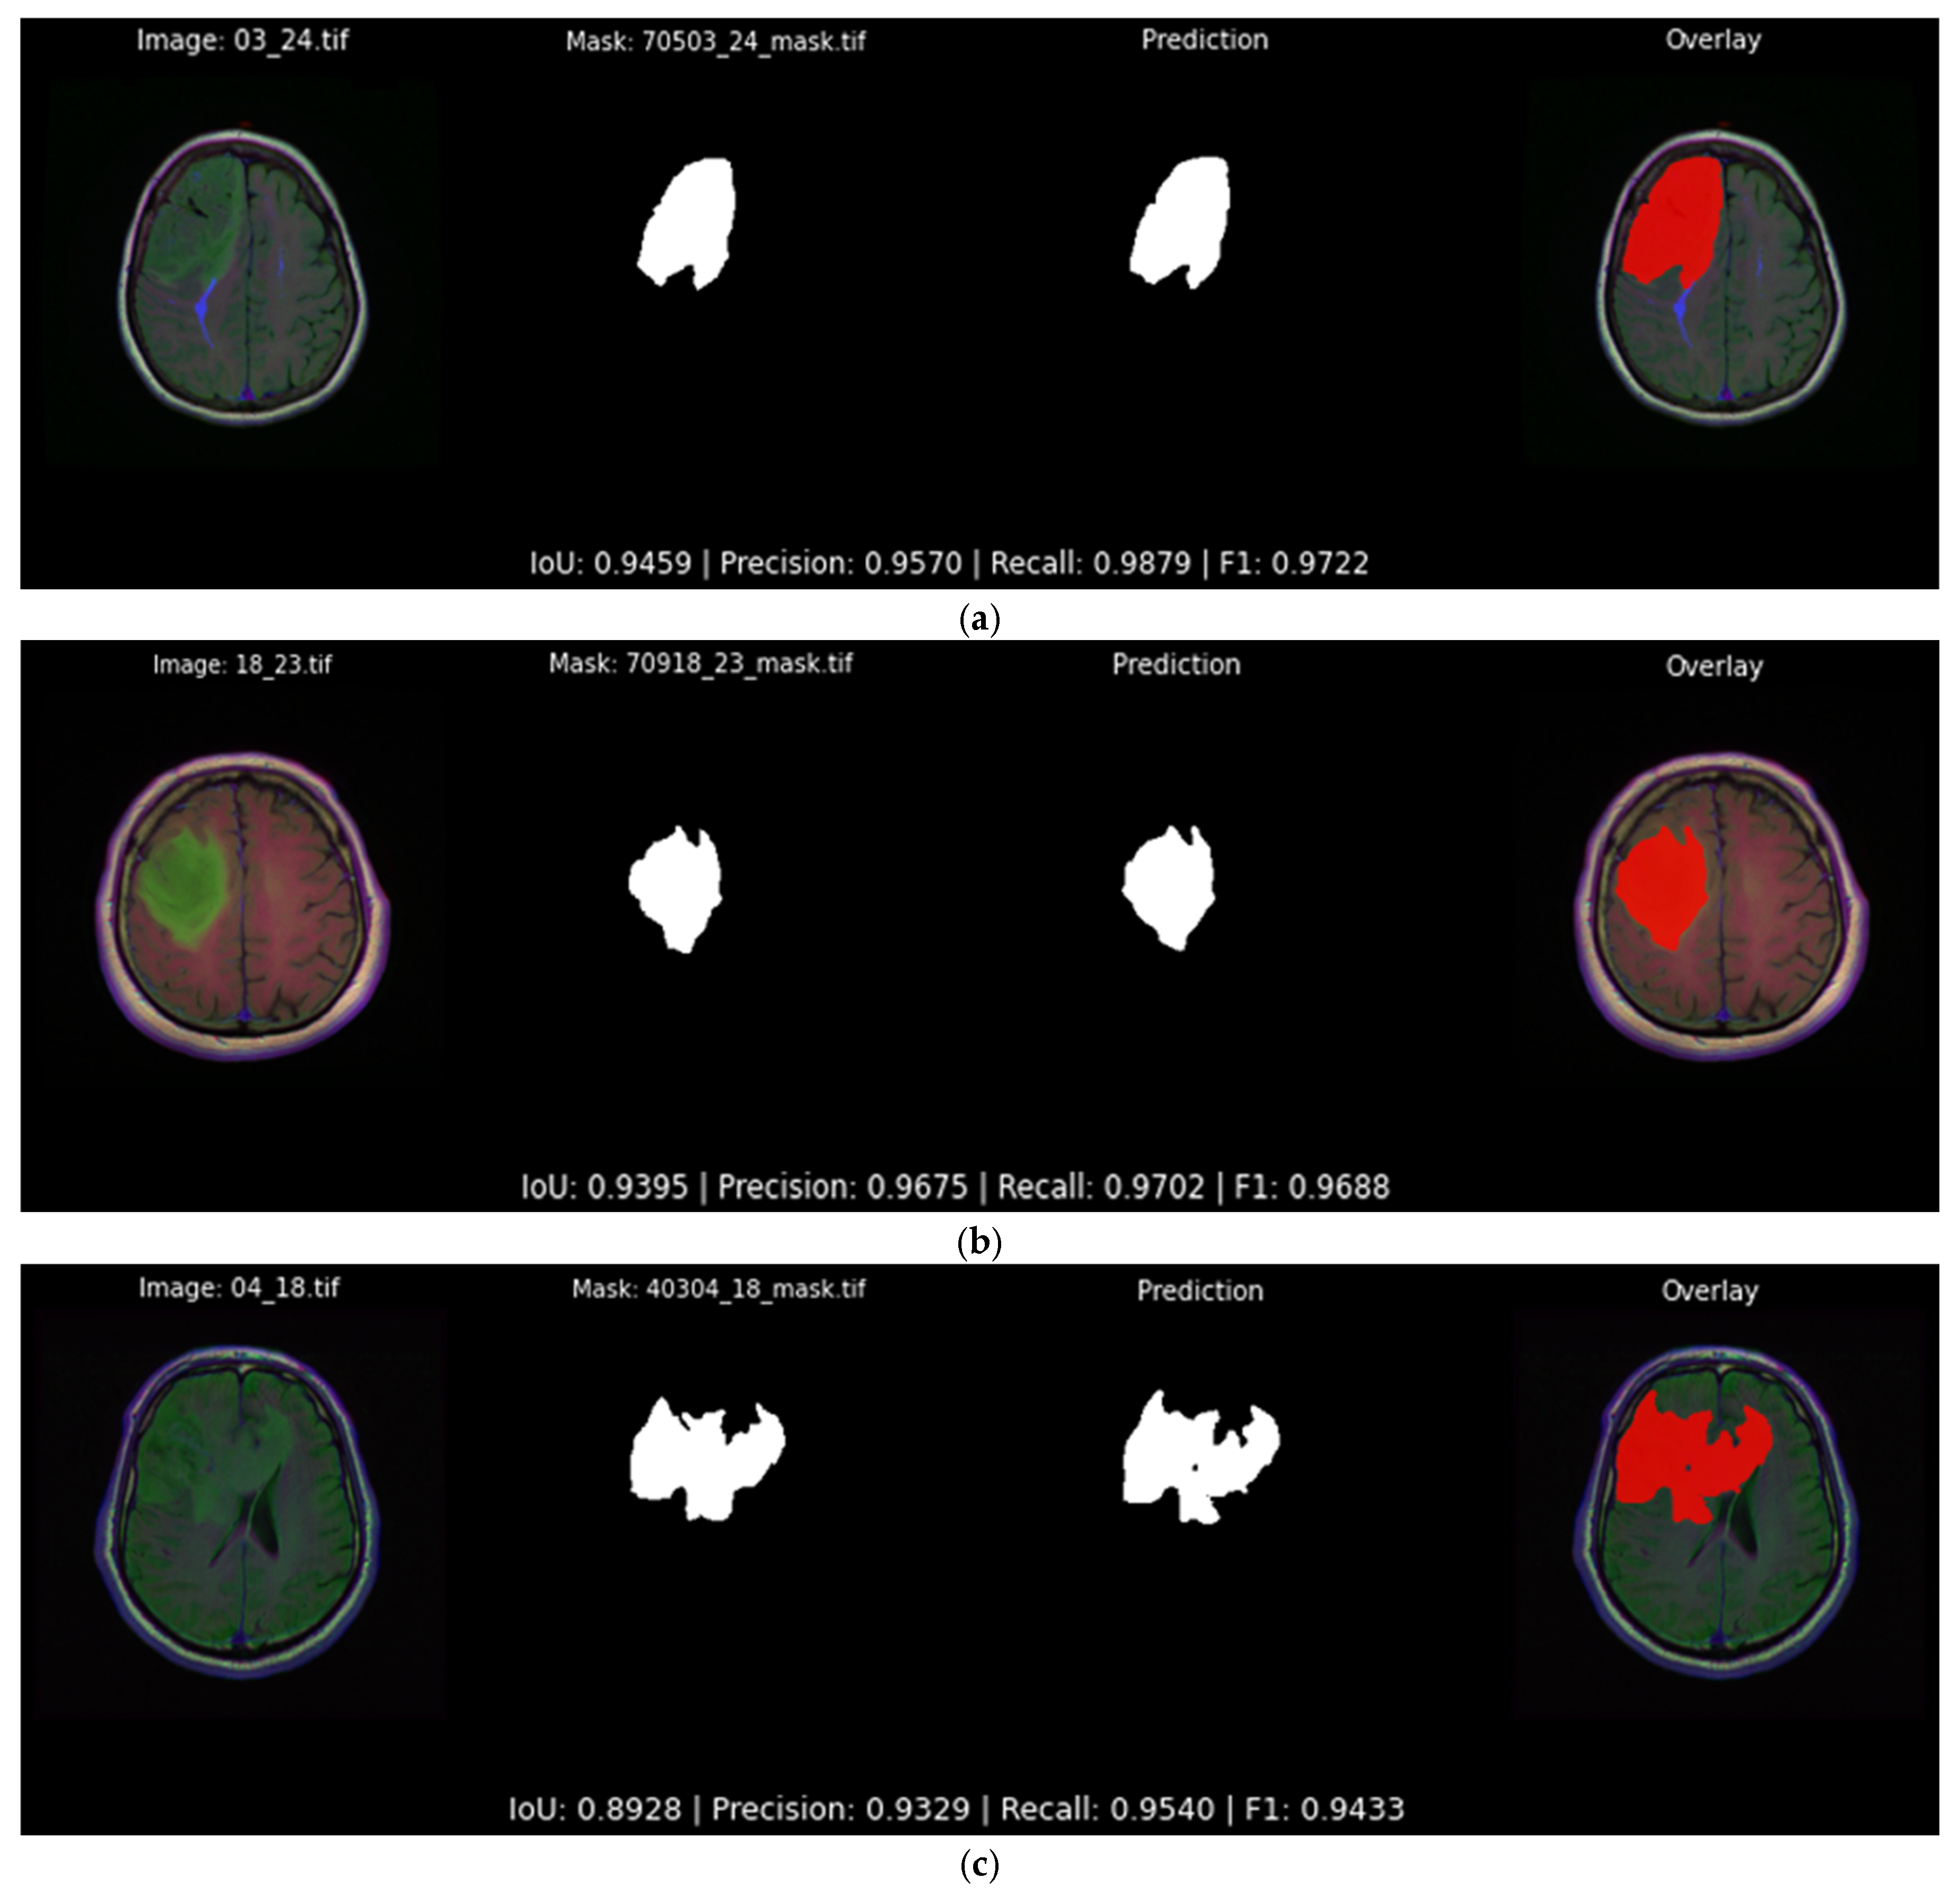

Figure 13 illustrates three typical highly accurate segmentations predicted by the best-performing softmax model presented in Table 5. All predictions follow the tumor boundaries closely, with IoU scores of 0.946, 0.940 and 0.892 for each example, respectively. In each case, the predicted mask aligns with the ground truth, not only predicting its general shape but also most of the details.

Figure 13.

Qualitative evaluation with examples in which the Attention U-Net and DiceBCE with softmax head predicts accurate tumor segmentation masks (IoU > 0.89). Each subfigure displays the original image, the ground truth segmentation mask, the predicted segmentation mask, and the original image overlaid with the predicted segmentation output mask (red) generated by the top-performing segmentation model: (a) showcases an example of a segmentation output of 0.945 IoU; (b) showcases an example of a segmentation output of 0.939 IoU; (c) showcases an example of a segmentation output of 0.892 IoU.